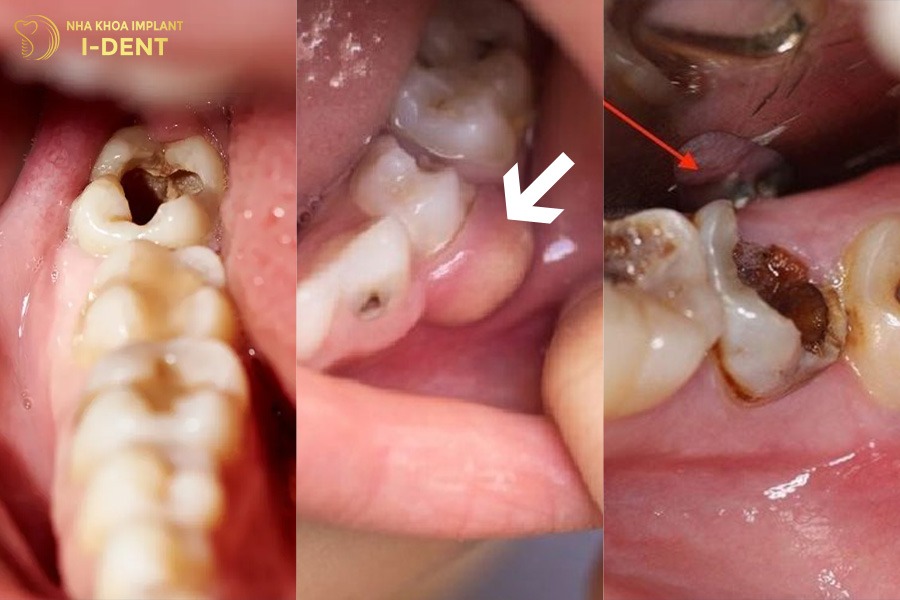

- Sâu răng: Răng số 6 mọc sớm (khoảng 6–8 tuổi) khi trẻ chưa biết cách chăm sóc răng miệng đúng nên dễ bị sâu. Khi sâu tiến triển nặng sẽ phá hủy men răng và ngà răng dẫn đến viêm tủy, áp xe hoặc gãy vỡ thân răng nên phải nhổ bỏ răng.

- Viêm nha chu quanh răng: Các bệnh lý viêm lợi, viêm quanh răng khiến mô nướu và xương ổ răng bị tiêu dần, chân răng yếu và lung lay. Khi tình trạng viêm trở nên nghiêm trọng thì răng số 6 không còn đủ độ bám vững chắc nên buộc phải nhổ để tránh lây lan sang răng kế cận.

- Tai nạn hoặc chấn thương gãy, vỡ chân răng: Các va đập mạnh do té ngã, tai nạn hoặc thói quen cắn vật cứng có thể làm nứt, gãy thân hoặc chân răng. Trường hợp tổn thương quá sâu không thể phục hồi sẽ dẫn đến mất răng số 6 vĩnh viễn.

Nguyên nhân gây mất răng số 6 lâu năm.